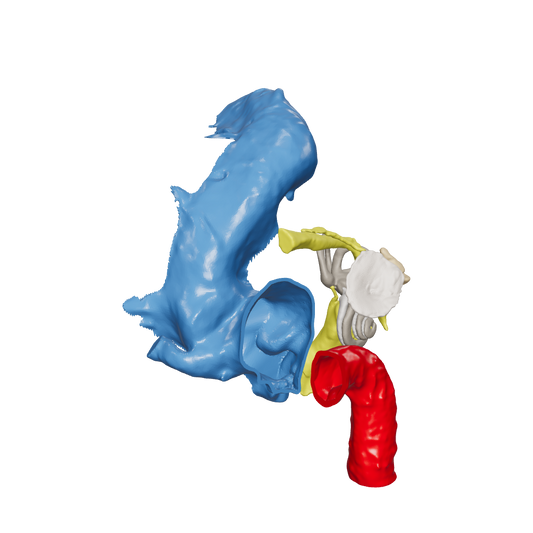

Dissect each one to learn human temporal bone anatomy, hearing and vestibular systems.

*High Contrast Colors* 3D Temporal Bones to Introduce Anatomy (6-pack)

Regular price $402.00 USDRegular priceUnit price per -